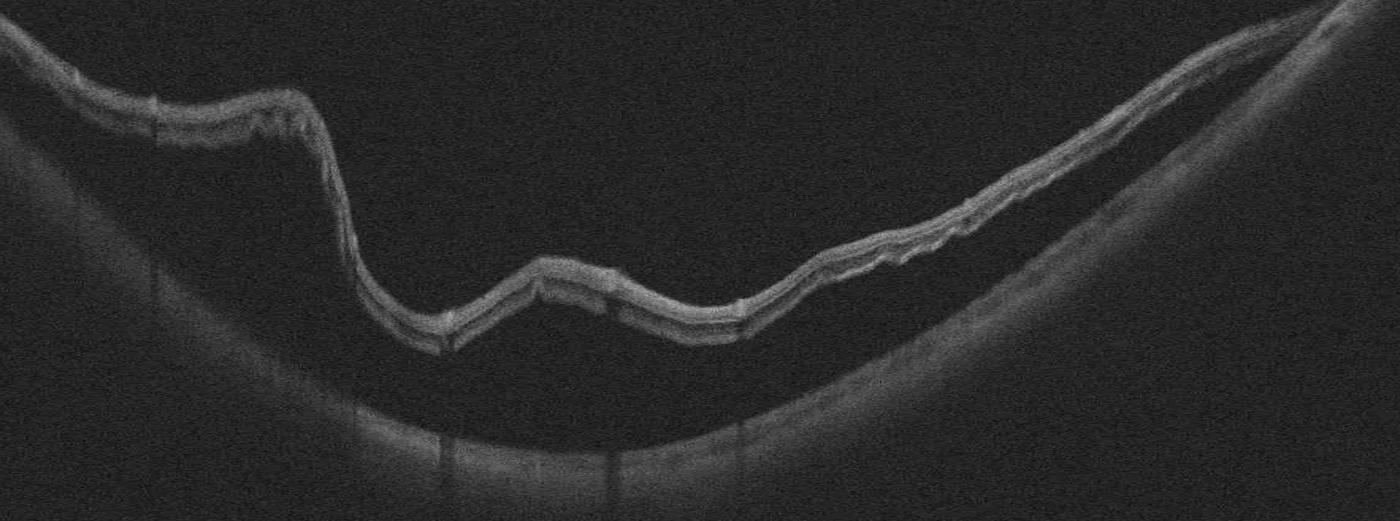

Trou maculaire

Ouverture au centre de la fovéa provoquant une tache noire centrale et des métamorphopsies. Classé en 4 stades selon la classification de Gass :

- Stade 1 : menace de trou — traction vitréo-maculaire focale, kyste intrarétinien. Pas de trou de pleine épaisseur. Surveillance.

- Stade 2 : petit trou de pleine épaisseur (< 400 microns), opercule partiellement attaché. Indication chirurgicale.

- Stade 3 : trou de pleine épaisseur (> 400 microns), décollement complet du vitré périfovéolaire. Chirurgie recommandée.

- Stade 4 : trou de pleine épaisseur avec décollement postérieur du vitré complet. Taux de fermeture chirurgicale > 90 %.

- Traitement : vitrectomie + pelage de la MLI + tamponnement par gaz (SF6 ou C3F8). Pour les grands trous maculaires (> 400 microns), une technique d'inversion de la membrane limitante interne (inverted ILM flap) est réalisée pour favoriser la fermeture.